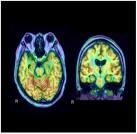

Previously, PET scans for many cancers would be reimbursed only if the PET facility submitted data to the NOPR. Now, all Medicare beneficiaries with certain cancers will be able to receive Medicare coverage for at least one PET scan, as prescribed by their physicians. The nine currently covered cancers—breast, cervix, colorectal, esophageal, head and neck, lymphoma, melanoma, non-small cell lung and thyroid—have all been expanded to cover the subsequent treatment strategy, in addition to initial diagnosis. Additionally, Medicare is now expanding coverage to include ovarian cancer and myeloma, making a total of eleven indications now covered for both the initial diagnosis and subsequent treatment strategy for patients. For all other cancers, PET coverage for subsequent treatment strategy evaluation requires participation in an approved Coverage with Evidence Development (CED) program, such as a modified NOPR.

NOPR was established in 2006 to track the utility of PET in patients with cancer. Studies, which analyzed data from more than 41,000 patients and were published in the Journal of Clinical Oncology and Journal of Nuclear Medicine, showed that the use of PET scanning led to an intended change in cancer management in more than one out of three cases.